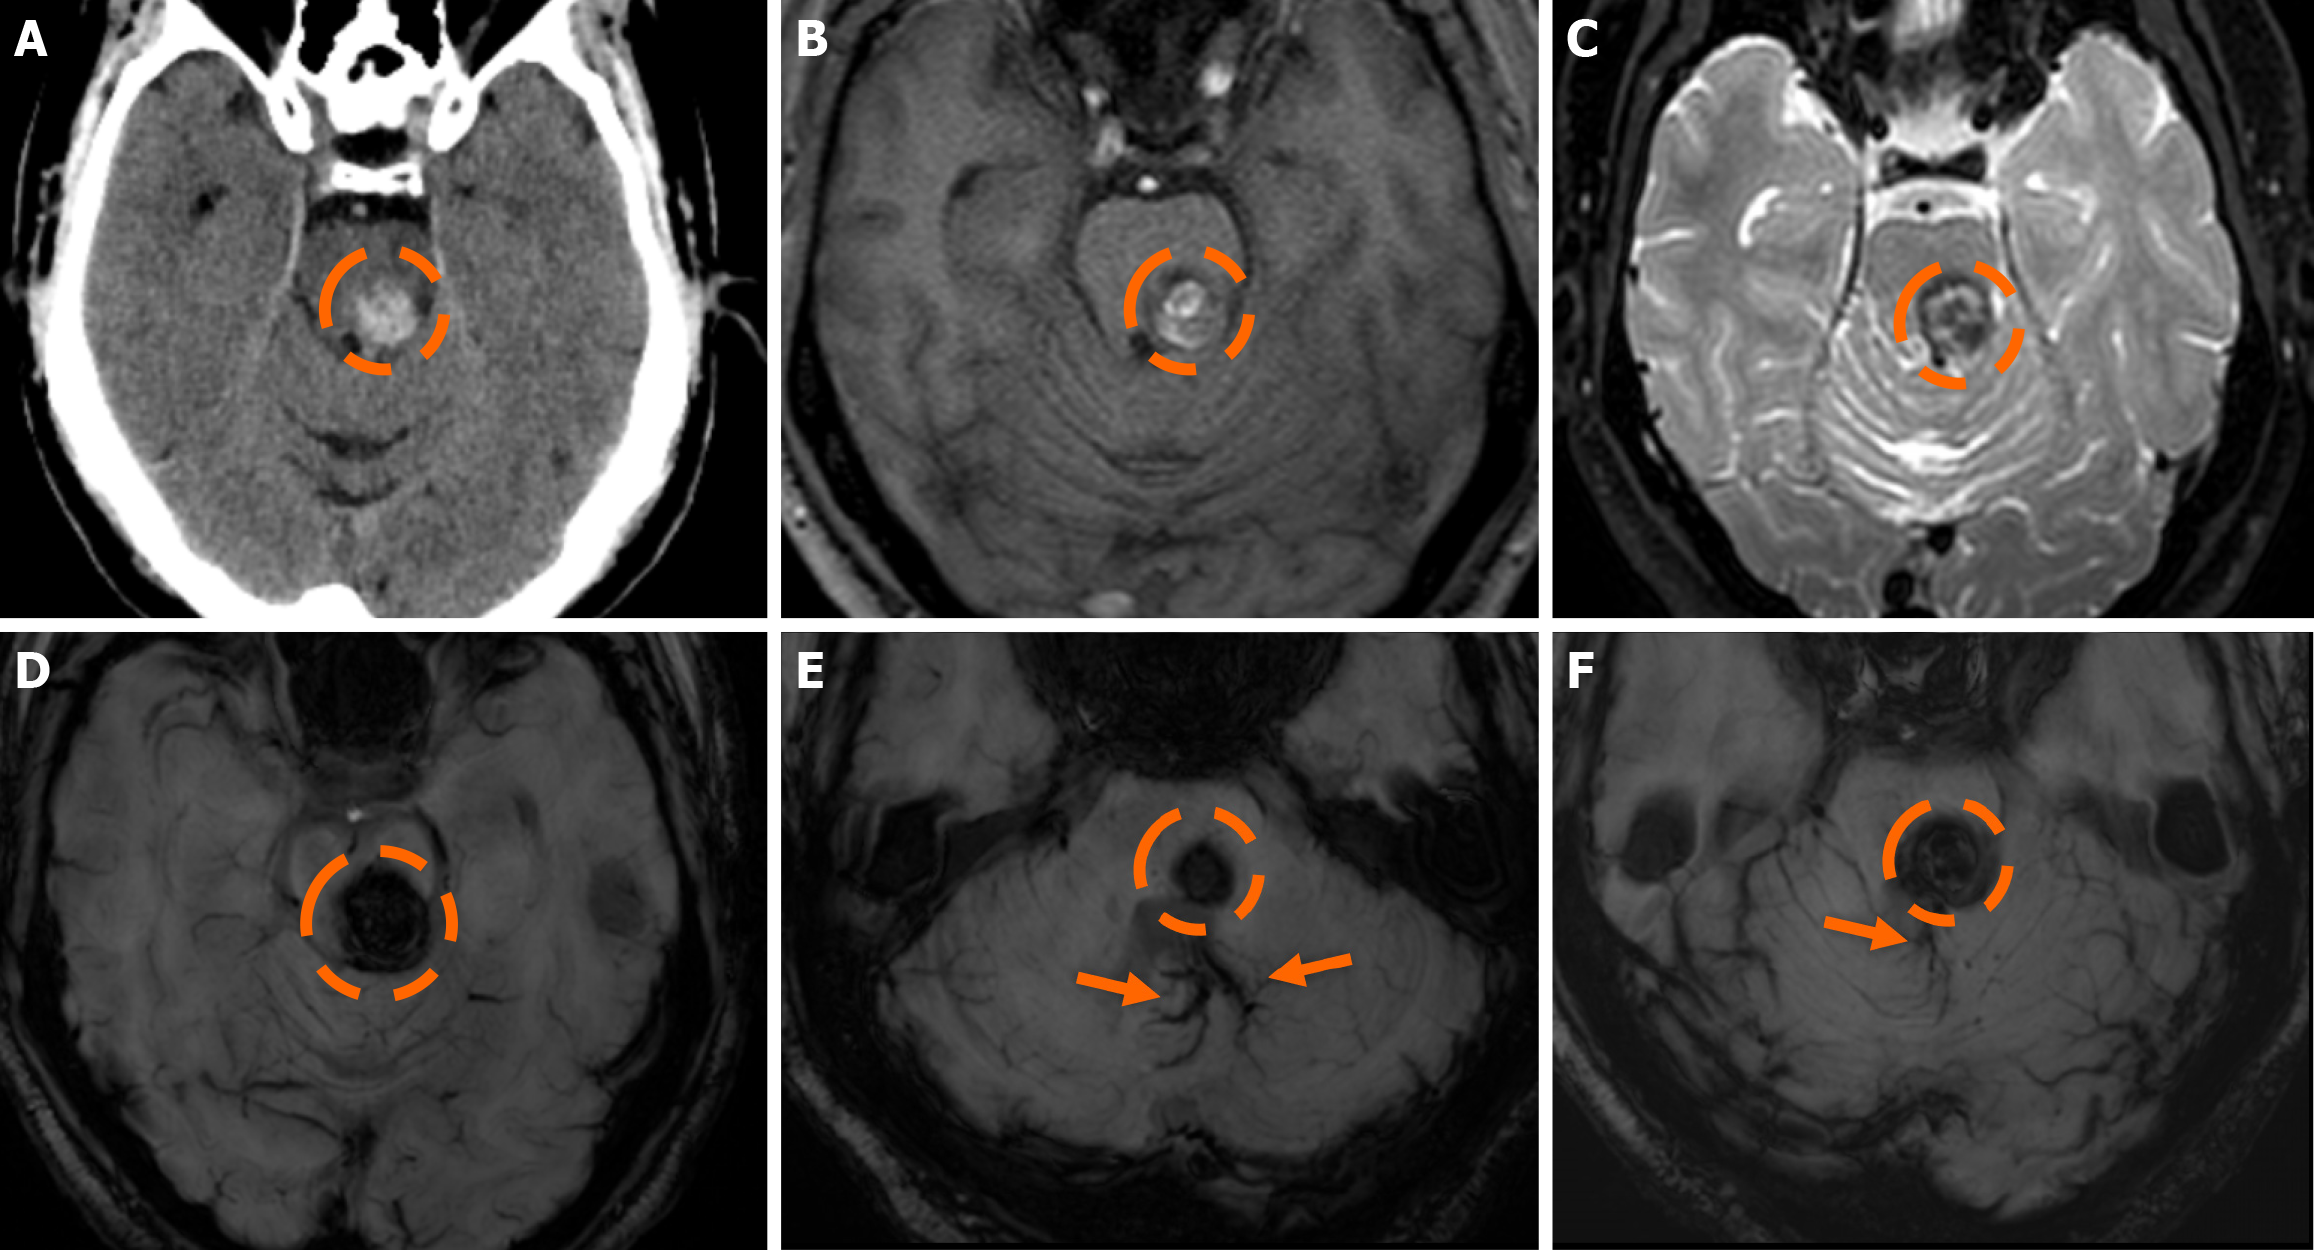

Functional MRI (fMRI) depends on blood oxygen level-dependent contrast, and changes are attributed to both extravascular tissue and local capillaries and veins. Theoretically, DVAs can contribute to the fMRI signal and can potentially lead to pseudoactivations during presurgical mapping[58]. Various examples of DVAs on CTs and MRIs are shown in Figures 1 and 2.

On non-contrast CT, smaller DVAs may not be visualized, while larger ones with a patent collecting vein may appear isodense or slightly hyperdense compared to the brain cortex. A thrombosed collecting vein may appear markedly hyperdense[45]. Non-contrast scans can also assess locoregional parenchymal abnormalities (i.e., calcifications) in the drainage territory[48]. Post-contrast brain CT, typically performed 2-3 minutes after contrast administration, provides clearer visualization of the characteristic “caput medusae” morphology and the collecting vein, both of which enhance[10]. A “caput medusae” morphology is defined as multiple radially oriented veins that converge centrally to the collecting channel[49]. Dedicated CT angiography, usually with bolus tracking, and/or venography with 50 second-delay can provide more information on the morphology of the DVA but are usually not necessary[3,5]. Some DVAs may show ampullary dilatation of their proximal portion at the convergence of the medullary veins[10]. Newer CT technologies with dynamic subtracted angiography provide more detailed morphological visualization[5].

DVAs are often detectable across various MRI sequences but are most clearly visualized on post-contrast T1-weighted (T1w) and susceptibility-weighted imaging (SWI) sequences[7]. Smaller DVAs can be overlooked, even in post-contrast series. In a study by Gökçe et al[7], almost half of the DVAs were not visible on non-contrast sequences. The collecting vein is more easily visualized than the “caput”[12]. DVAs typically appear as flow voids on both T1w and T2w sequences and may demonstrate phase-shift artifact[3]. The radicles may sometimes have a high signal at fluid-attenuated inversion recovery (FLAIR) images, which should not be confused with parenchymal changes[51]. They show homogeneous enhancement after gadolinium contrast administration. Their visualization is enhanced by three-dimensional (3D) gradient-echo (GE) T1w sequences, which provide high-resolution imaging and allow for multiplanar reconstructions[45]. Application of 3D sequences can also allow better morphological assessment, such as stenosis of the collecting vein[5]. MR venography and time-of-flight angiography are usually not necessary, and their role is to evaluate whether there are signs of arterial components[4]. Nonetheless, non-arterialized but large DVAs may also be visualized at time-of-flight images.

SWI is very sensitive in detecting pathologies that cause inhomogeneity of the magnetic field[45]. A DVA appears as a low-signal structure on SWI and T2* sequences. In phase imaging, its signal remains consistent with other veins but is inverted relative to that of calcifications[45]. SWI provides a more detailed assessment of the entire structure and has been shown to be more sensitive than conventional T2*-weighted imaging. SWI is not significantly affected by low velocities, making it very effective to assess low-flow lesions such as DVAs[52,53]. SWI in high and ultra-high field strengths (3T and 7T) can better visualize a DVA[54].